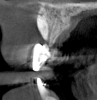

Fig 10. Tomographic images of teeth Nos. 6 (Fig 10), 7 (Fig 11), and 8 (Fig 12) clearly showed vertical gains in alveolar height, including in the edentulous area corresponding to tooth No. 7. The apex of tooth No. 8 was located within the soft tissue because it was force-erupted beyond its socket.

Figure 10

After 3 months of post-orthodontic stabilization, a cone-beam computed tomography scan was taken to re-evaluate the results and plan the future treatment sequence. Tomographic images clearly showed vertical gains in alveolar height, including in the edentulous area corresponding to tooth No. 7 (Figure 10 through Figure 12). The apex of tooth No. 8 was forced-erupted beyond its socket and could be visibly located within the soft tissue.30,33